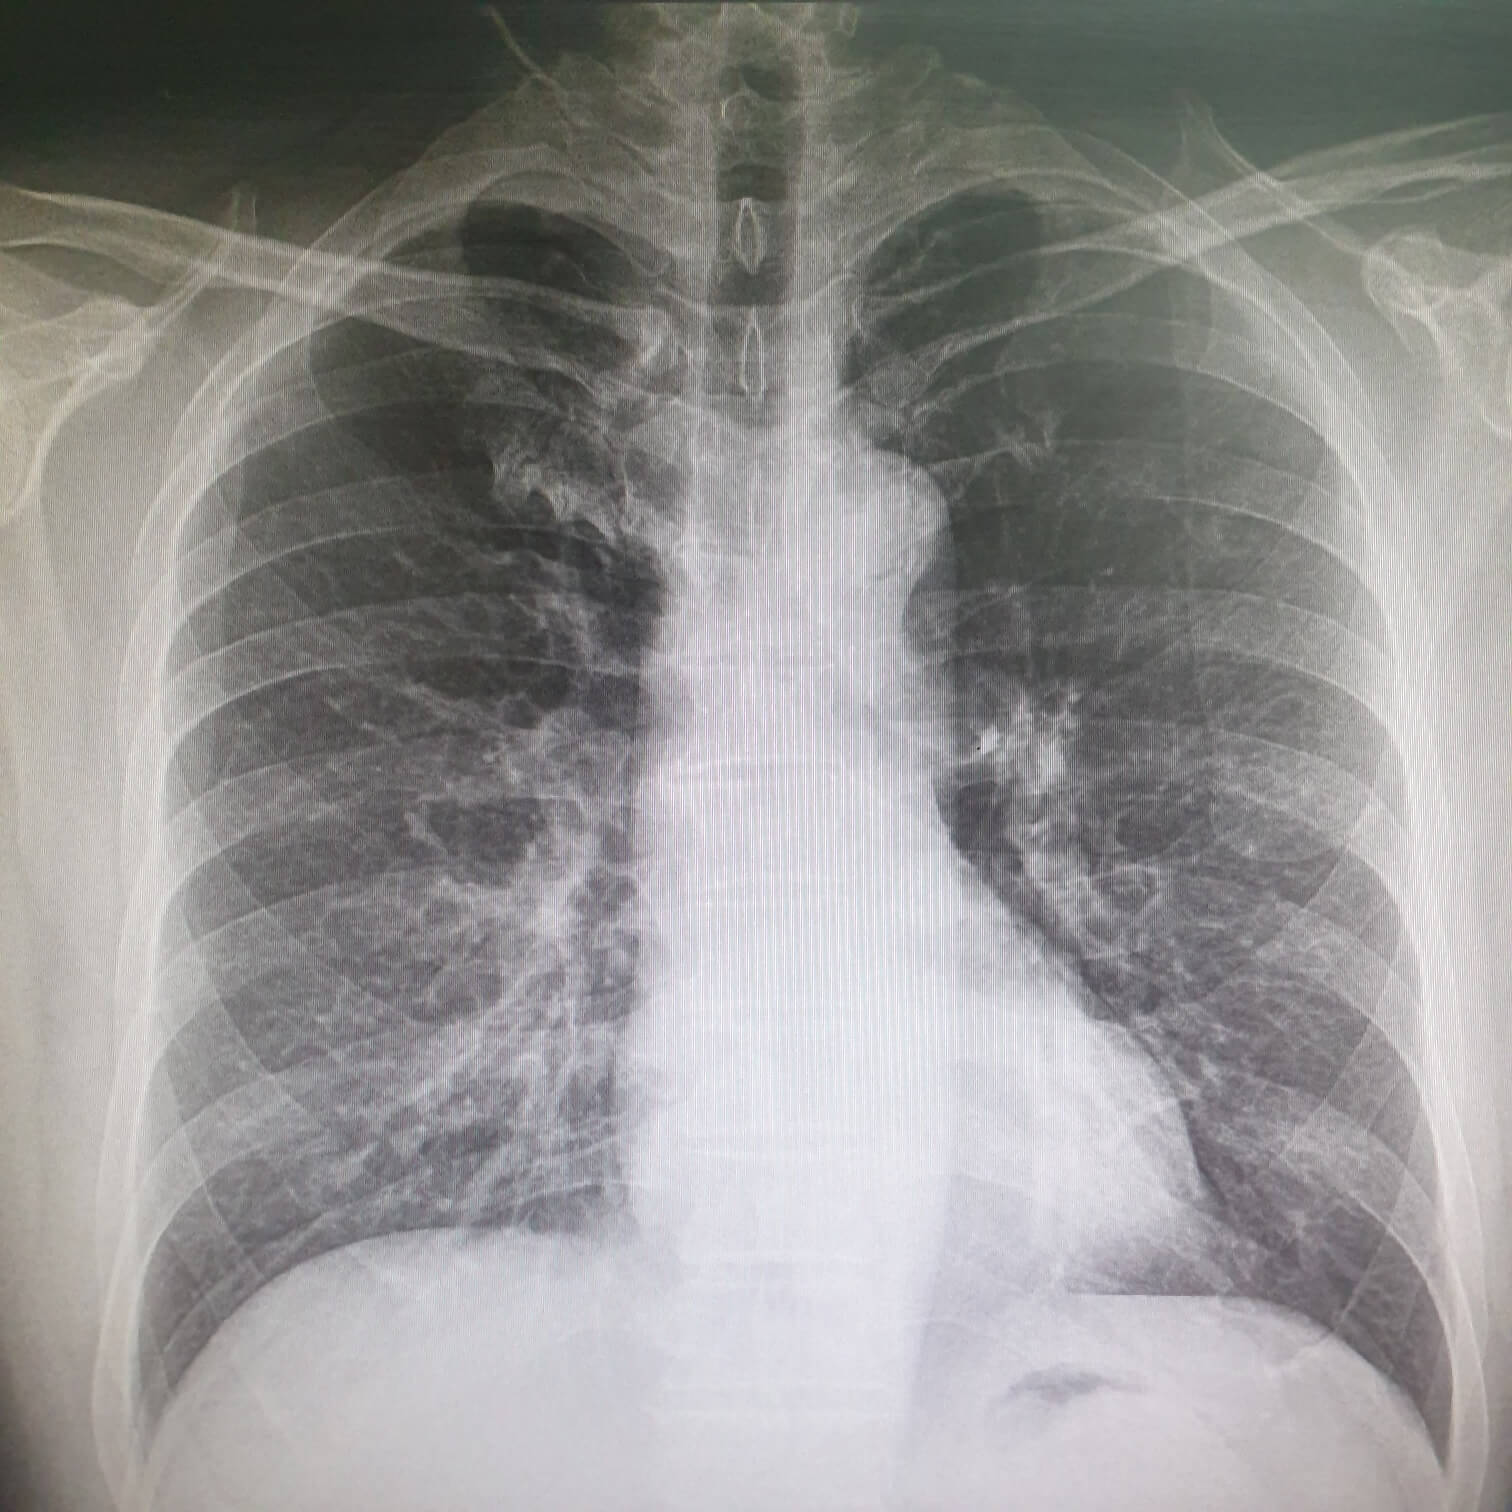

수술 전 흉부 X-ray 검사

흉부 X-ray 검사는 가장 기본적인 폐 관련 검사입니다.

특히 인공호흡기를 사용하는 전신마취의 경우 수술 후 폐렴등의 호흡기 합병증의 발생 가능성이 높으므로 폐질환 여부를 판단하기 위하여 시행합니다.

수술 전 환자 폐의 상태가 전신마취가 적합한지 부적합한지를 평가하는 방법이며 검사상 폐기능의 저하가 확인되면 폐기능 검사를 통해 폐의 기능 상태를 정밀검사하게 됩니다.